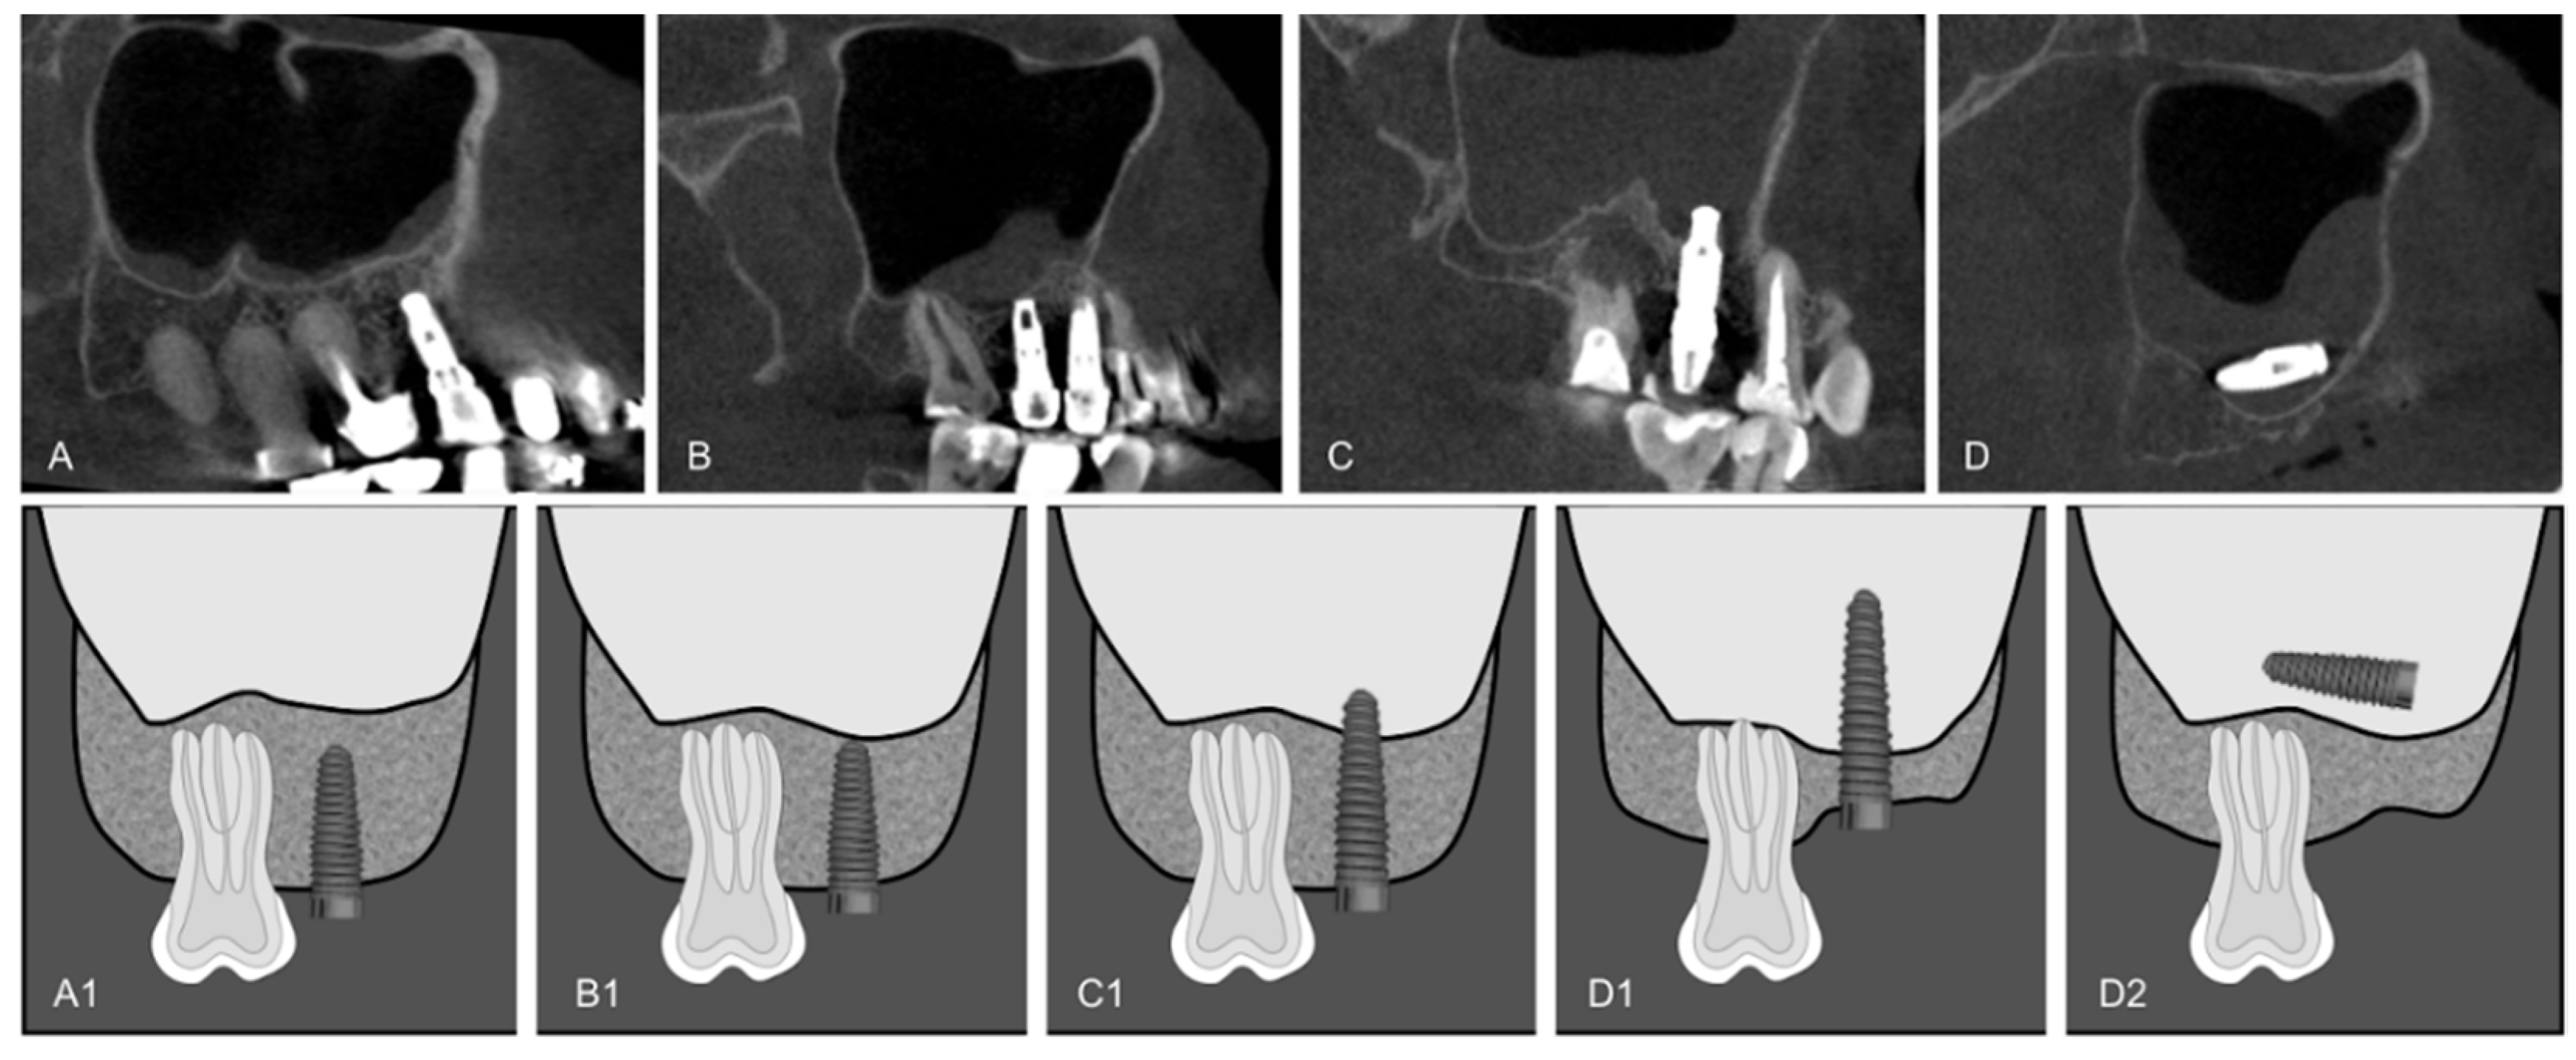

Diagnostics Free FullText Evaluation of the Maxillary Sinus of

From www.mdpi.com

Diagnostics Free FullText Evaluation of the Maxillary Sinus of Bone Density Requirements For Dental Implants Most studies using ct and dental cbct to evaluate the bone mineral density at dental implant sites have assessed multiple. The amount of bone required for a dental implant can vary depending on individual factors. As bone density is directly related to bone strength, bone density at the site for implant insertion can be determined by the tactile. The external. Bone Density Requirements For Dental Implants.